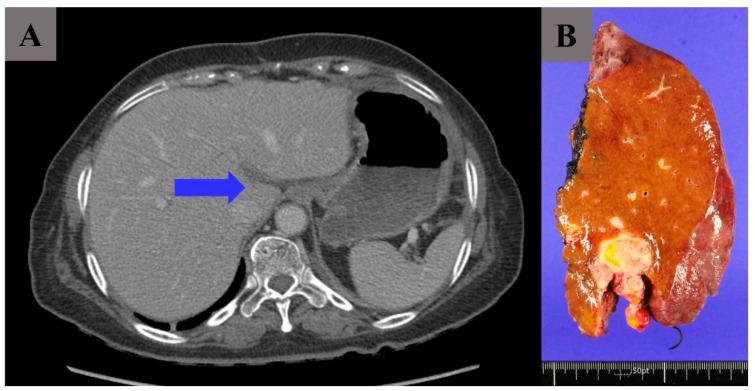

The objective of this study is to investigate the surgical, clinical and pathological outcomes of left hemi-hepatectomy during cytoreductive surgery (CRS) in patients with primary ovarian cancer. The electronic medical charts of patients with primary ovarian cancer who received CRS including left hemi-hepatectomy from 2000 to 2023 were reviewed and retrospectively analyzed. A total of 17 patients underwent left hemi-hepatectomy for resection of a deep peritoneal implant in the round ligament of the liver during primary CRS. Among these 17 patients, hepatic parenchymal invasion was confirmed in 10 patients (58.8%). Tumor distribution of others is as follows: Glisson's capsule, hilum, falciform ligament and gall bladder. Fourteen patients (82.4%) achieved CRS; the remaining three patients had residual tumors less than 1 cm. The median period to subsequent chemotherapy was 21 days (range, 12-35 days). No specific complications related to left hepatectomy were identified such as liver failure or bile leakage. Left hemi-hepatectomy for complete surgical resection of a deep peritoneal implant of the round ligament of the liver is surgically feasible and safe.

本研究的目的是调查原发性卵巢癌患者在减瘤手术(CRS)期间进行左半肝切除术的手术、临床和病理结果。回顾并回顾性分析了2000年至2023年接受包括左半肝切除术在内的CRS的原发性卵巢癌患者的电子病历。共有17例患者在初次CRS期间接受了左半肝切除术,以切除肝圆韧带中的深部腹膜种植灶。在这17例患者中,10例(58.8%)证实有肝实质侵犯。其他患者的肿瘤分布如下:肝门部、肝门、镰状韧带和胆囊。14例(82.4%)患者实现了CRS;其余3例患者的残留肿瘤小于1 cm。后续化疗的中位时间为21天(范围为12 - 35天)。未发现与左肝切除术相关的特定并发症,如肝衰竭或胆漏。通过左半肝切除术完全切除肝圆韧带的深部腹膜种植灶在手术上是可行且安全的。